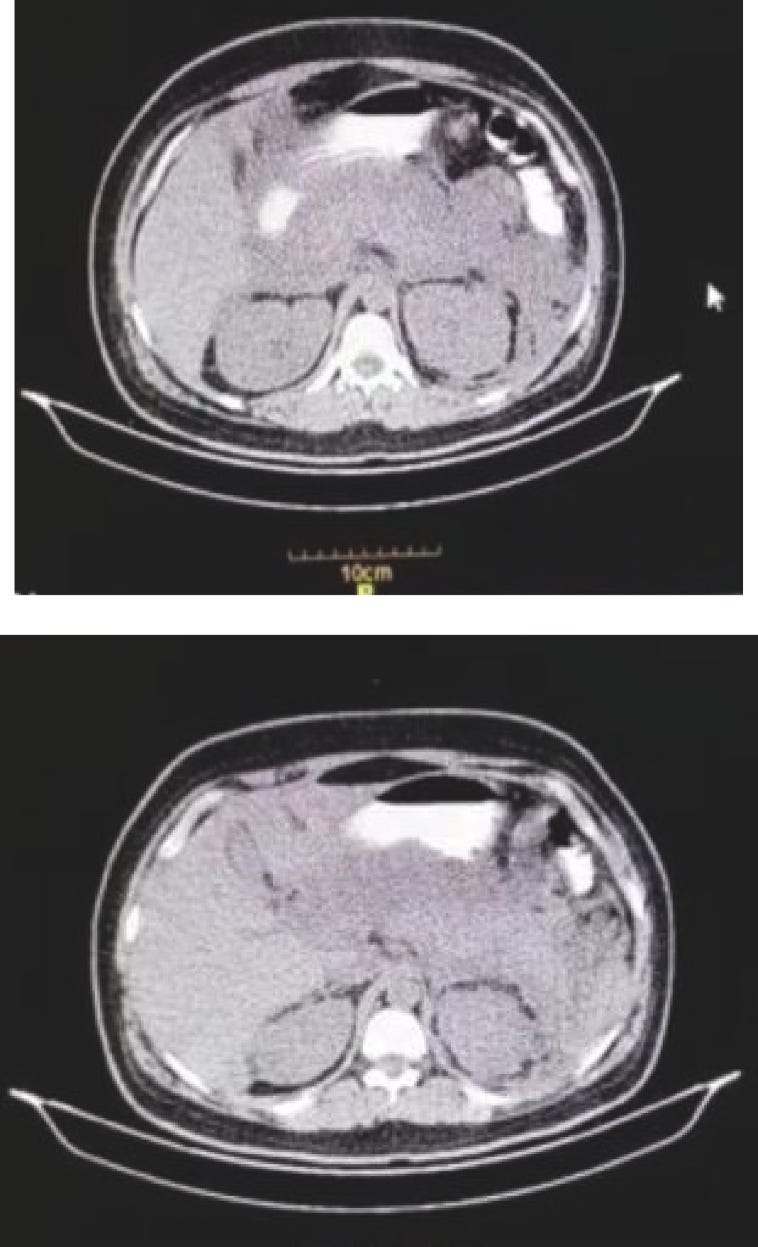

Computed Tomography (CT) scan of the abdomen. Homogeneous enlargement of the pancreas, extensive peri-pancreatic fat and peri-pancreatic fluid was observed.

Acute pancreatitis following COVID-19 vaccine: A case report and brief literature review